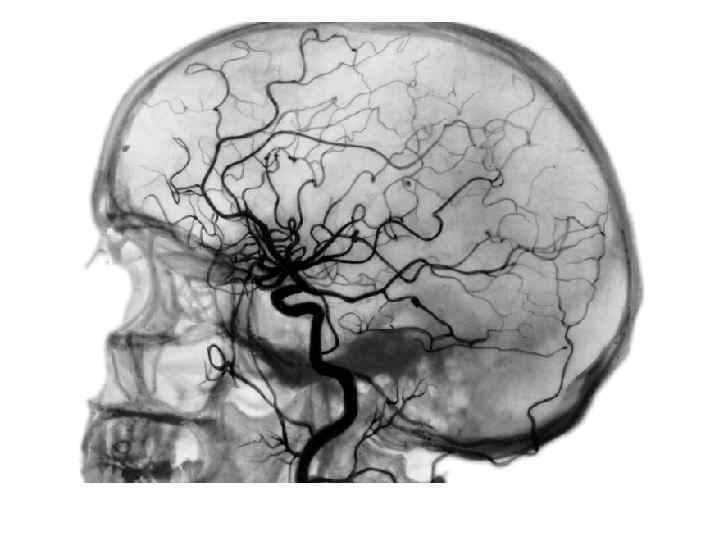

Магнитно-резонансная ангиография высокоинформативный и безопасный метод получения изображения кровеносных сосудов при помощи магнитно-резонансного томографа, позволяющий оценить анатомические и функциональные особенности кровеносных сосудов интересующей области. Метод МРангиографии позволяет своевременно обнаружить нарушения кровообращения и назначить соответствующее лечение. Кроме того, на основании данных ангиографии может проводится планирование оперативных вмешательств на сосудах, таких как ангиопластика, коронарография и стентирование сосудов.

Магнитно-резонансная ангиография 2 Метод магнитно-резонансной ангиографии (МР-ангиографии) основан на отличии сигнала подвижной ткани (крови) от окружающих неподвижных тканей, что позволяет получать изображения сосудов без использования каких-либо рентгеноконтрастных средств. Тем не менее, для получения более чёткого изображения применяются особые контрастные вещества на основе парамагнетиков (гадолиний).

М. Р. ангиография